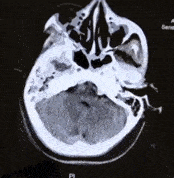

第一次CT 【左】

CT检查提示:中脑基底部和中脑被盖之间,桥脑出血,量约2ml

保守治疗2天后,病情加重,瞳孔进一步扩大,出血量增加

出血部位波及到桥脑、延髓,量约有5ml,生命体征开始出现不稳定